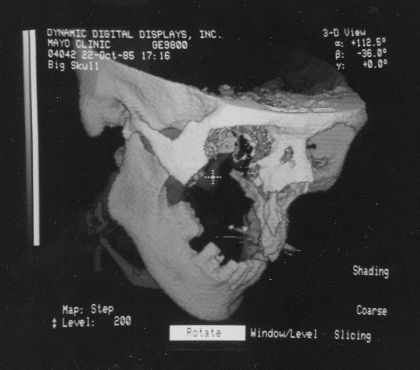

The following VS1 screen-shots were found in a binder along with the VPP photos and hundreds of 35 mm slides of all sorts of stuff:

Voxelscope I Screen Shots. First Row: Multiplanar Reformatting; Second Row: 3-D Shaded Surface

The annotation was generated by the software so no more cutting and pasting. :)

The pair of video monitors was the focus of the booth, displaying sequences of skulls and such from real CT datasets like those in the above photos being rotated, sliced, and diced at reasonably rapid update rates. The instructions for performing the operations were captured and recorded but the actual voxel processing was done in real-time based on the stored program. Thus, no one needed to be constantly spinning the trackball, though that could have been arranged upon request. :) The monitors were up high so visitors couldn't get close enough to see how poor the resolution was. :( :) It is believed that VS1 had a microcode-based pipeline running at 10 MHz so that a 128-cube (2,097,152 voxels) could be manipulated at around 5 images per second. The display was 256x256 pixels on a 60 Hz non-interlaced display - double that of VPP. But object space could be configured to be any arbitrary rectangular prism as long as all the data fit into the voxel processor's memory. The photos, above, are typical of the displays at RSNA.

These photos of the Voxelscope II screen are typical of the types of rendering provided by the system.

Voxelscope II Screen Shots. Combination of 3-D Shaded Surface, Multiplanar Reformatting, and Segmentation